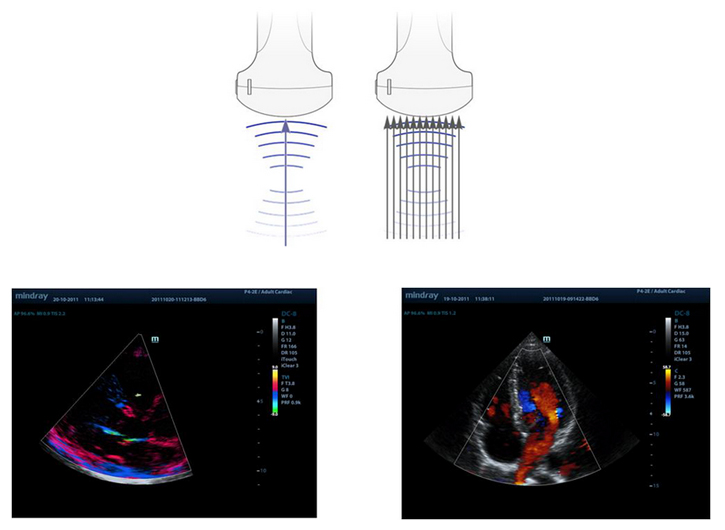

Multi-Beam-vorming

Maximaal 12 keer voor ├®├®n uitgezonden bundel, wat leidt tot uitstekende tijdresolutie en een grotere framesnelheid.

iBeam?

Hierdoor kunnen meerdere scanhoeken worden gebruikt om ├®├®n beeld te vormen, wat leidt tot een verbeterde contrastresolutie en verbeterde visualisatie